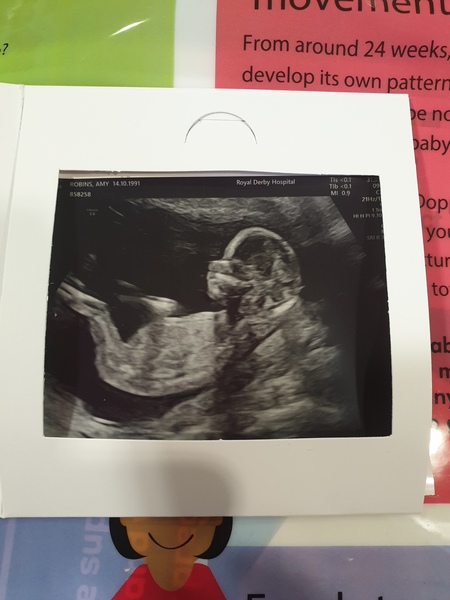

Aimzxo · 31/08/2019 10:08

My little bubs is dur January 31st

Got my gender scan in 2 weeks but would love to know people's opinions

Anyone any good at guessing genders of scan pictures